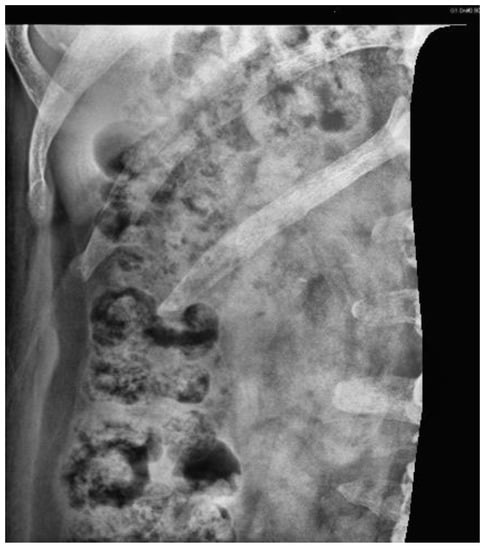

2.2. Datasets

3.4. Subsystem 2—Segmentation Model for Medical Images